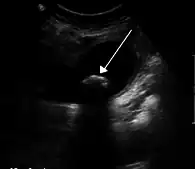

La colique hépatique est souvent liée à des calculs biliaires

Une colique hépatique (une douleur qui n'a rien de colique et rien d'hépatique, le nom plus approprié étant "douleur vésiculaire") est un symptôme douloureux ressenti par un patient dans la partie supérieure droite de l'abdomen. Cette douleur est généralement isolée ; elle ne s'accompagne pas de fièvre, d'altération de l'état général ou d'ictère. Elle peut s'accompagner d'une fièvre et d'un ictère dans la triade de charcot ou de villard. C'est une douleur généralement déclenchée par un repas riche en graisse (entrainant une augmentation de la CCK --> contraction vésicule biliaire).

On retrouve ce symptôme, par exemple, lors de l'expulsion d'un calcul hors de la vésicule biliaire (en même temps que la bile), lors de la contraction de celle-ci. Le calcul provoque une douleur vive en se déplaçant dans les voies biliaires : cette douleur peut irradier jusqu'aux côtes et l'épaule du côté droit.